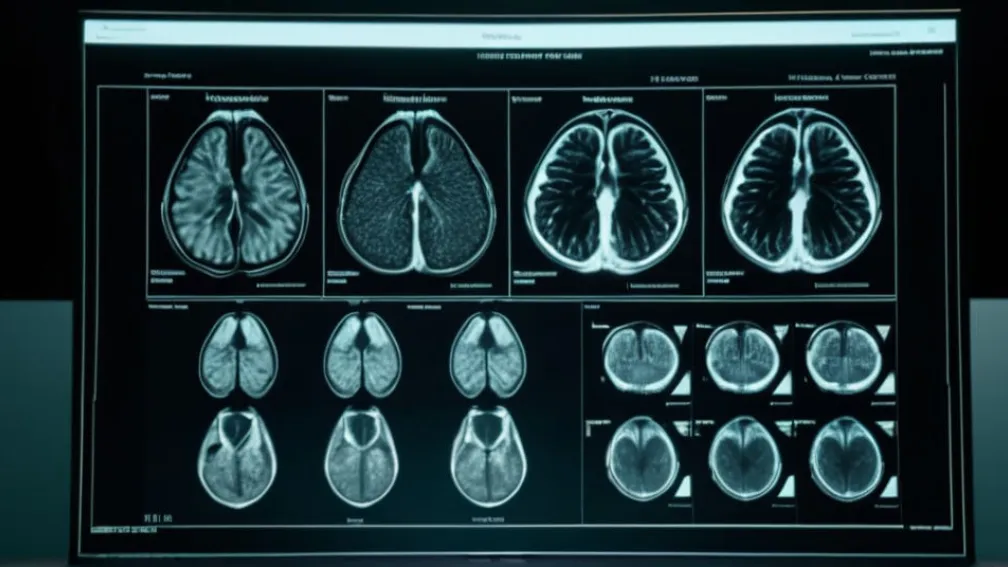

Після тижнів спекуляцій щодо стану здоров'я колишнього президента США Дональда Трампа, його особистий лікар, доктор Шон Барбабелла, оприлюднив результати магнітно-резонансної томографії (МРТ), проведеної у жовтні.

Прессекретарка Білого дому Кароліна Левітт зачитала меморандум, у якому детально йшлося про те, що МРТ черевної порожнини Трампа не виявила жодних аномалій. У документі наголошується, що "всі важливі органи виглядають дуже здоровими та добре кровопостачаються".

"Всі досліджені функції знаходяться в межах норми, без гострих чи хронічних захворювань. Підсумовуючи, це детальне обстеження відповідає стандарту медичного огляду для керівників віку президента Трампа та підтверджує, що він продовжує перебувати у відмінному загальному стані", — заявила Левітт.

У меморандумі також підкреслюється "відмінний" стан його серцево-судинної системи. Раніше цього року здоров'я Трампа викликало численні запитання, зокрема через повідомлення про набряки щиколоток та загадкові плями на руці. У липні Білий дім повідомляв, що президент страждає на "хронічну венозну недостатність".

Сам Дональд Трамп описав свої результати МРТ як "ідеальні". На борту Air Force One у розмові з журналістами він пожартував, що "не знає", яка частина його тіла була сканована, але додав, що це не був мозок, оскільки він успішно пройшов когнітивний тест.